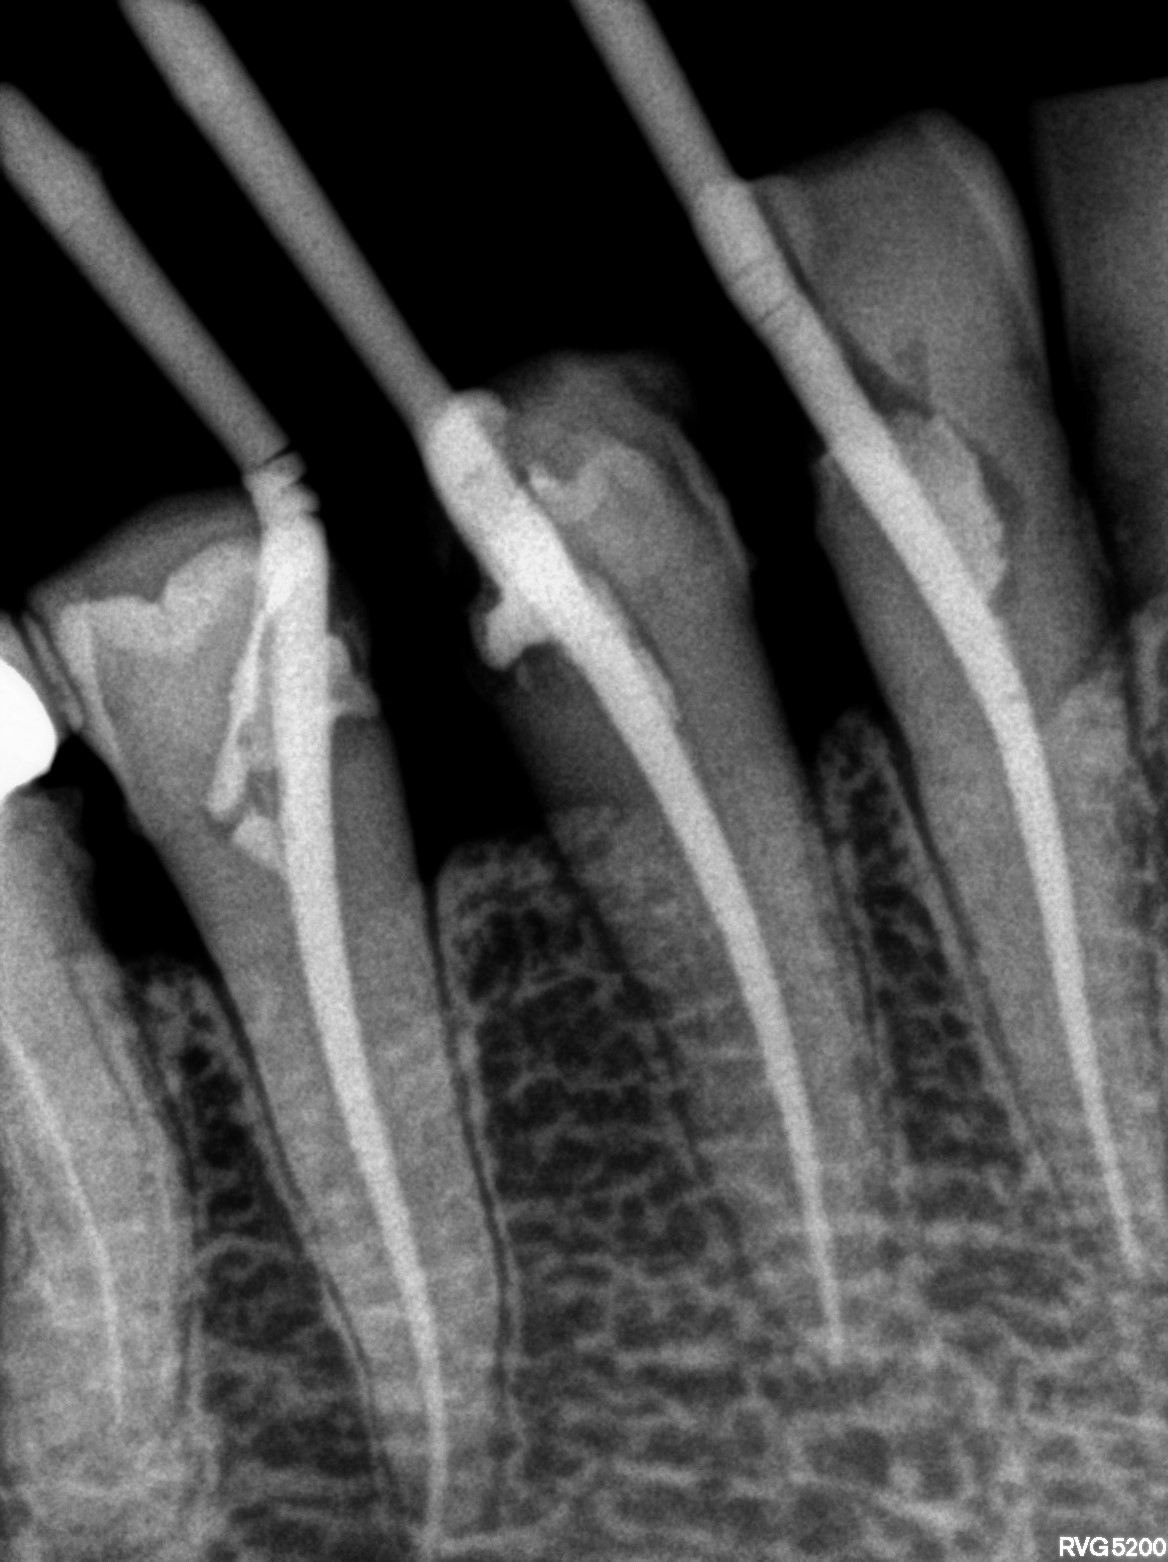

Dental Radiographs FHIR: DocumentReference · LOINC 24641-7

R56.jpg

24641-7